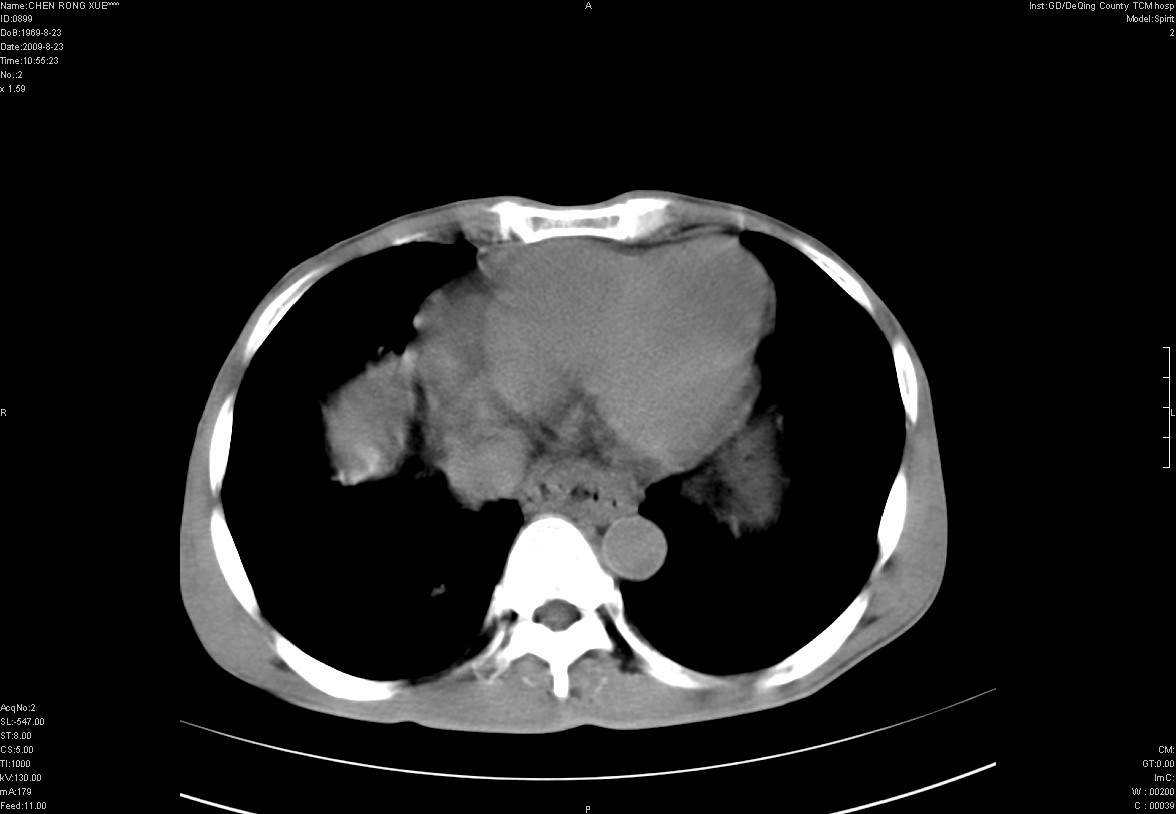

以下是引用zxl51642在2009-8-23 12:56:00的发言:[br]1、肝硬化、脾大;2、慢性胆囊炎;3、右肾占位并右侧腰大肌受侵,考虑恶性可能性大,建议增强扫描进一步检查。

以下是引用qiuleiyu在2009-8-23 15:17:00的发言:[br]1、慢性肝病,肝硬化,脾大,门脉高压。胆囊小结石。[br]2、右肾明显肿大,伴片状低密度灶,累及右侧腰大肌,肿瘤及炎症性病变皆有可能大,建议增强。

以下是引用zjzjr在2009-8-23 17:42:00的发言:[br]1、慢性肝病,肝硬化,脾大,门脉高压。胆囊小结石。[br]右肾脓肿波及肾周,建议增强